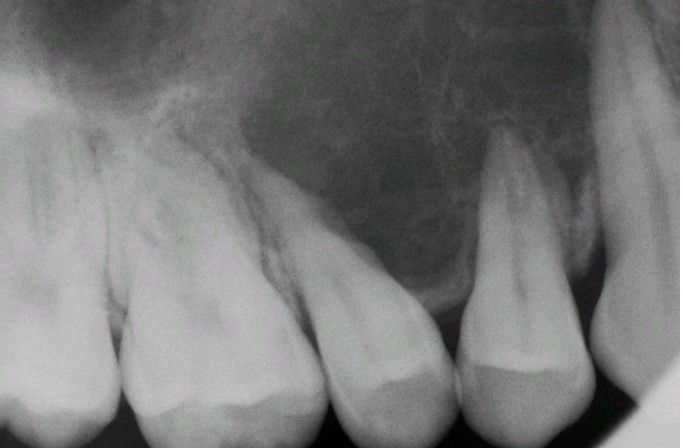

Mesenchymal Chondrosarcoma.

Periapical radiograph showing an ill-defined radiolucency with associated root resorption.